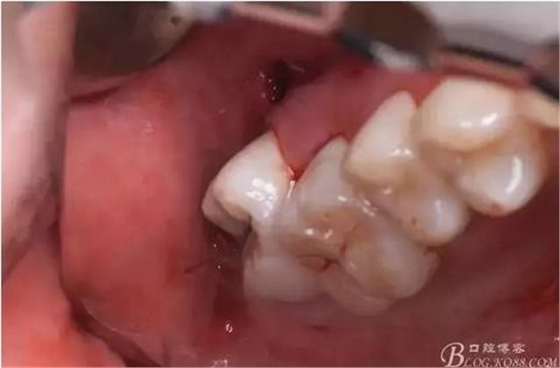

圖13.暴露骨面、去骨,露出18牙冠

圖14.暴露出18整個(gè)頰側(cè)比較好